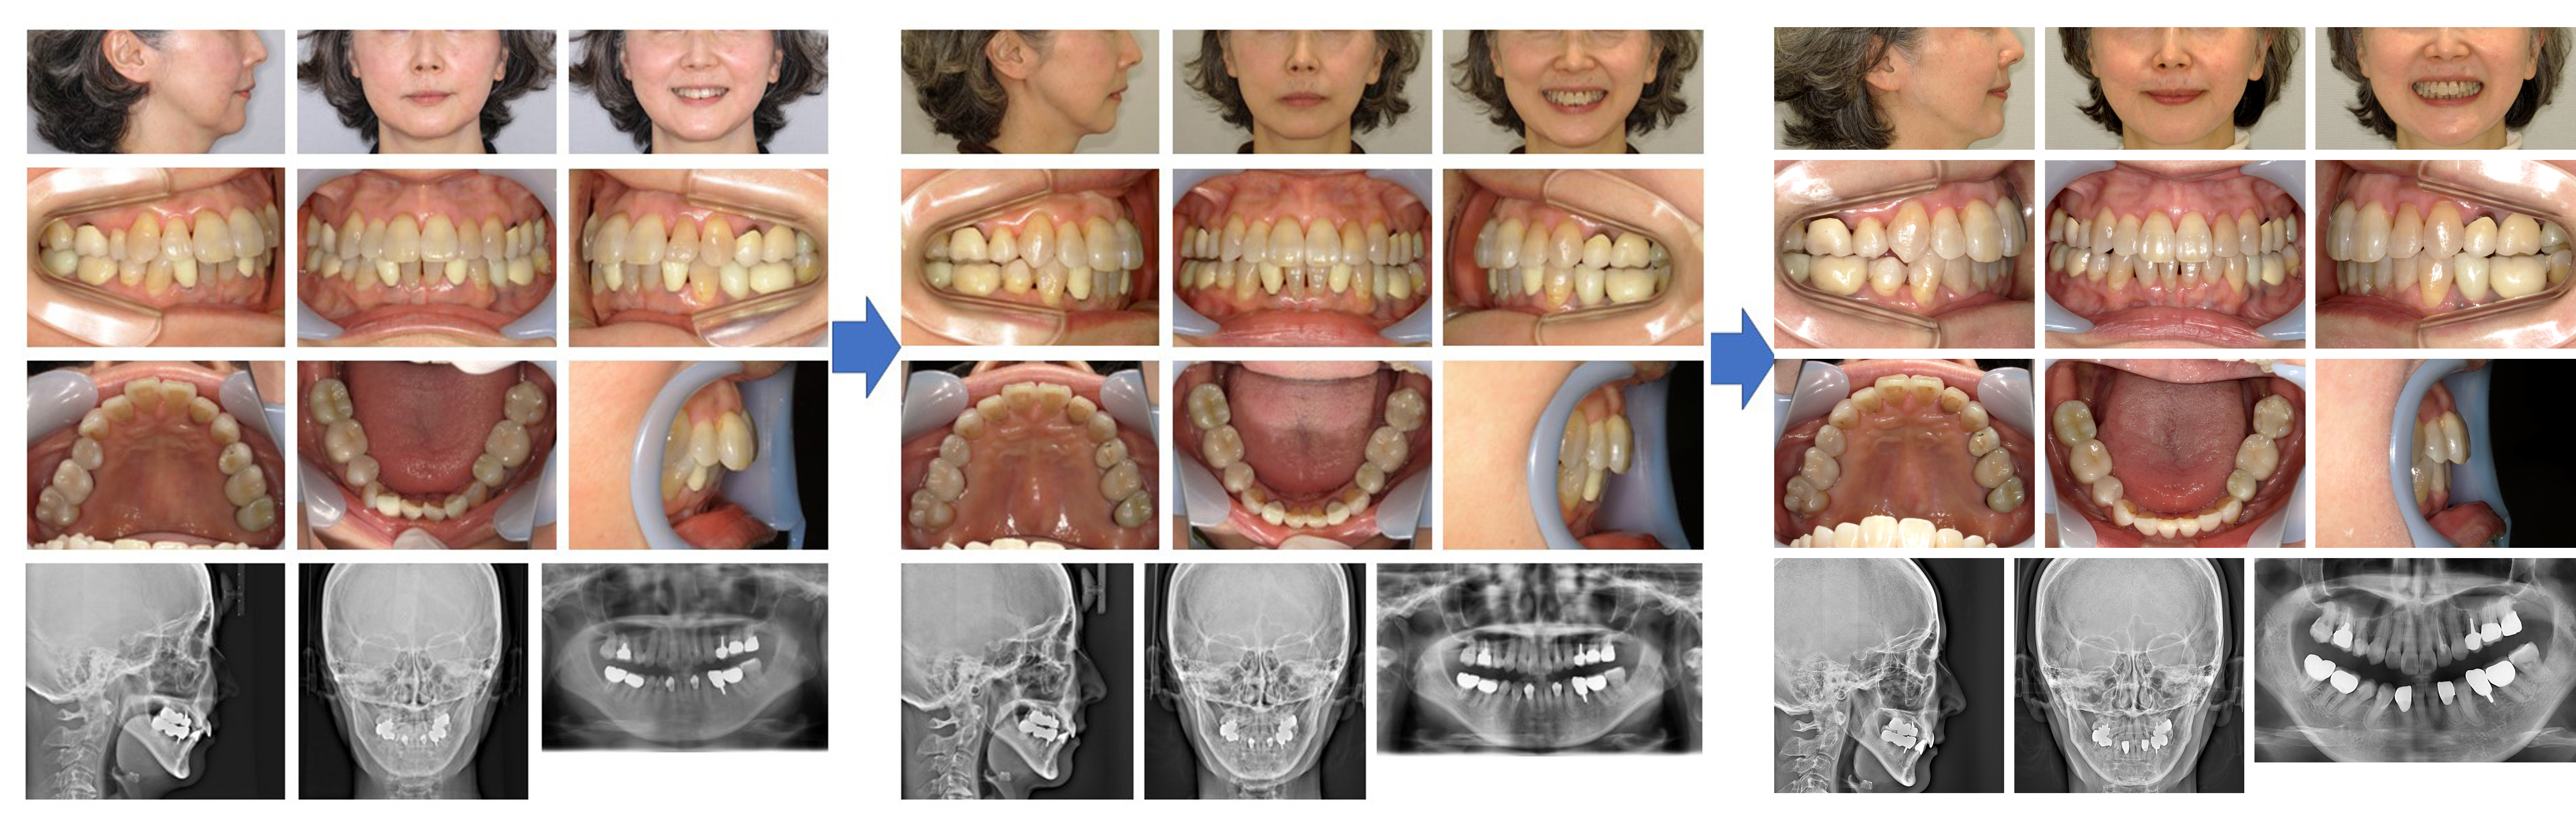

【治療例】初診時年齢:75歳9か月 / 性別:女性 / 主訴:歯がガタガタで食べ物が詰まりやすい

治療の概要:この症例は、マウスピース型(アライナー型)矯正装置(インビザライン®)を用いて非抜歯で治療した症例である。

補綴物が多く認められたため、補綴物やアタッチメントの脱離をしたものの比較的短期間で治療を終えた。

主訴:歯がガタガタで食べ物が詰まりやすい

診断名:アングルⅠ級叢生

使用した主な装置:マウスピース型(アライナー型)矯正装置(インビザライン®)

抜歯/非抜歯および抜歯部位:非抜歯

※こちらの症例は2022年3月から2023年9月に行った矯正治療です(現在も経過観察中)

治療期間:1年7か月

治療回数:20回